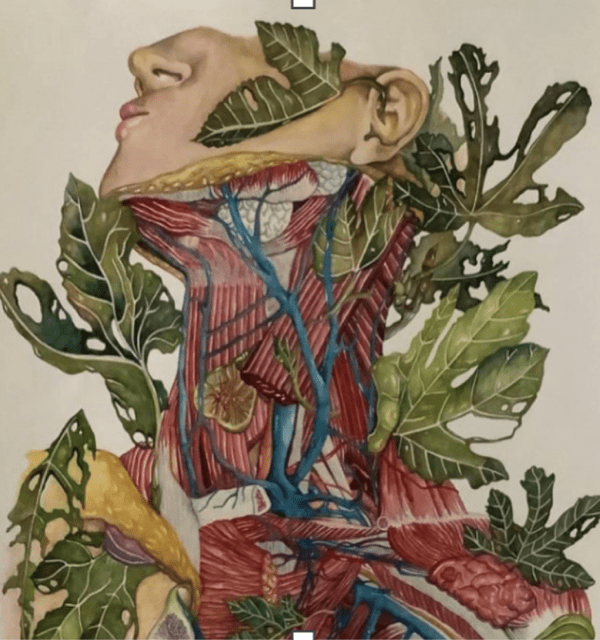

There is an expanding gap between my mind and spirit and my body.

I am a foreign body I do not recognize.

I must move most of my belongings out of the physical world

I have found a new address for my stuff. It is in the cognitive and spiritual world

I have become a poem.

My experiences and thoughts are no longer linear.

My stories are not cohesive.

I lost my glue.

There is no plot, no beginning, middle, or end. No path to follow cleared from the forest.